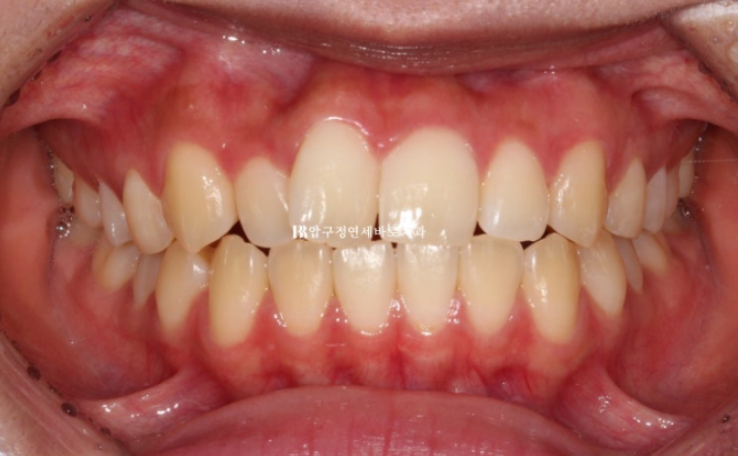

그리고 한달 후 24년 6월 드디어 치료를 마무리 했습니다.

24.06

배열은 가지런해졌고 앞니 교합도 처음에 비하여 깊어졌습니다.

유지장치까지 붙은 모습입니다.